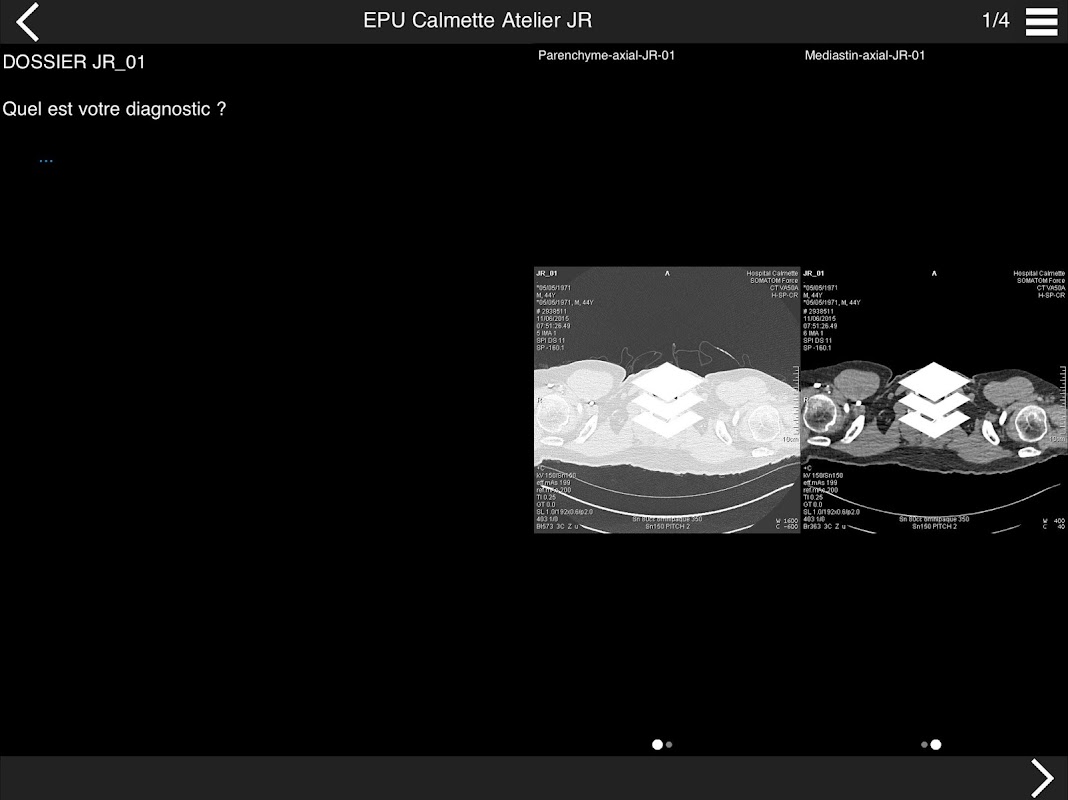

Retrouvez les cas cliniques du Cours intensif de TDM multicoupe du thorax dans cette application.

Thèmes du cours 2017 :

ACTUALISATION DES PROTOCOLES

* BPCO et nodules pulmonaires : recommandations en 2017

* Pathologie interstitielle : lésions élémentaires et « patterns »

* Pathologie vasculaire et médiastinale

* Oncologie thoracique : bilan standard et introduction à l’étude de l’angiogénèse

* Amiante : images pièges et discordances des secondes lectures.